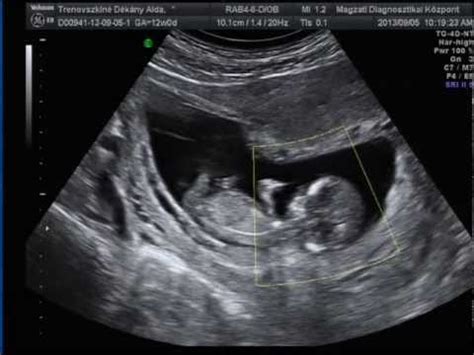

I. trimeszteri (12-13 hetes) ultrahang szűrővizsgálat

A terhesgondozás kötelező része, mely a 11. hét 0 nap és a 13. hét 6 nap között történik. A vizsgálat célja a terhességi kor pontos meghatározása, a durva fejlődési rendellenességek, kromoszóma rendellenességek gyanújának felismerése. Vizsgáljuk a magzat koponya formáját, az orrcsont meglétét vagy hiányát, valamint az orr mögötti háromszöget. A vizsgálat egyik legfontosabb része a tarkóredő (NT) lemérése, amelynek megvastagodása utalhat szívhibákra, valamint a Down-, Patau-, Edwards-szindróma, vagy más kromoszóma-rendellenességek megnövekedett kockázatára is. Vizsgáljuk a magzat szívének struktúráit és a véráramlást, az alapvető magzati anatómia ábrázolását, a végtagokat és a gerincet. Ekkor történik a koponya körfogatának (HC) és átmérőjének (BPD) lemérése, a haskörfogat (AC) és a combcsont hossza (FL). Megítélhető a magzatvíz mennyisége, vizsgálható a méhlepény elhelyezkedése.